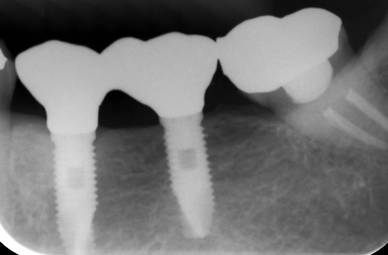

ストローマンインプラントとスプラインインプラント

ストローマンインプラントとスプラインインプラントが隣り合わせに埋入されています.このころストローマンからスプラインに変えています。変えた理由は前歯部の審美性に優れていること、アバットメントの自由度があること、抜歯後すぐに埋入できるなどでした。

6年後。犬歯にコンポジット充填。第一大臼歯はメタルボンドになりました

8年後ほとんど変化がありません